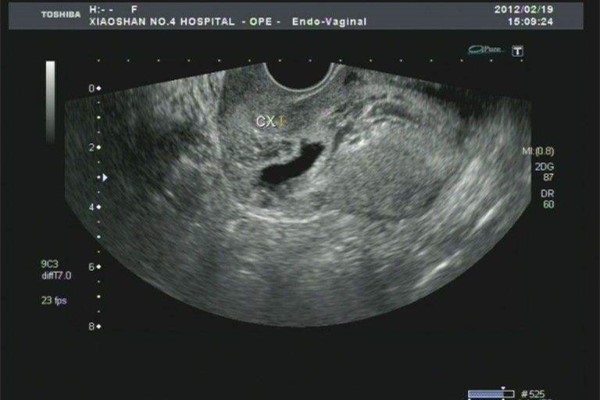

很多二胎孕妈都在担心一个问题,疤痕子宫二胎厚度的标准是多少?其实,如果你是疤痕子宫,那么你子宫的厚度应该在0.3cm以上才可以,如果低于0.3cm的话那么就说明你的子宫有点薄。

一般妊娠期间的子宫厚度低于3mm的情况,就要提前终止妊娠,也就是说需要提前做剖腹产,防止到了后期,子宫太薄发生子宫破裂的危险!

由此可见,生二胎再次印证了并不是说想生就能轻轻松松生的,有疤痕子宫的孕妇会有很大的妊娠风险!只要疤痕子宫在妊娠期间,子宫的厚薄不低于0.3cm就可以继续妊娠,如果小于这个厚度的话,那么就只好选择提前剖腹产了,以免后面抱抱太大导致子宫破裂!生二胎,还是要谨慎啊!